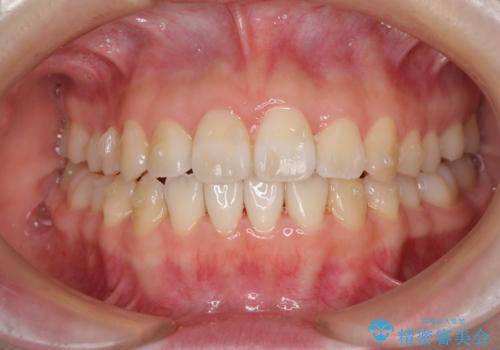

- 前歯の捻れと、ちょっとした出っ張りを気にして来院された患者様です。

歯と歯の間を削る(IPR)ことでデコボコを解消し、インビザラインで整えることとしました。

インビザライン治療特有の奥歯が接触しない時期が続き、当初予定よりも期間がかかりましたが、最終的には安定した咬み合わせと、整った前歯になりました。